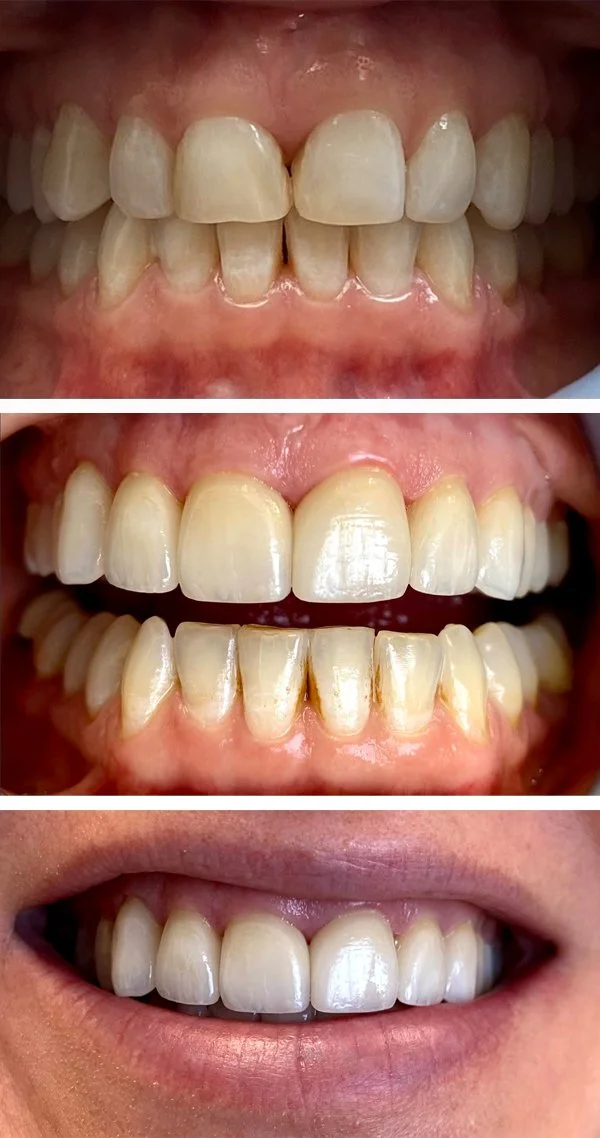

Cosmetics

We can improve the appearance of your teeth in a way tailored to you. Crowns, veneers, tooth shaping, and dental bonding may be used.

Bioclear restorations

Dental Bonding

Veneers

Tooth reshaping

Crowns

Bioclear Restorations, bonding

Restoration

Crown and Bridge